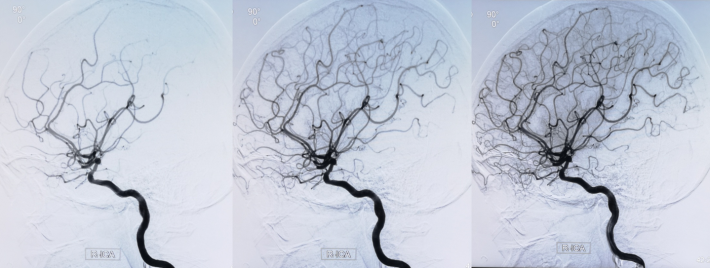

4.5mm*22mm Enterprise 支架

术 后

✔支架选择:左侧颈内动脉虹吸段狭窄段长度较长,远端至左侧大脑中动脉M1起始段,近端至眼动脉开口上方。且此段血管迂曲,狭窄段近端、远端都有较大的血管转折,使用球扩支架风险很高。因此我们选用了顺应性较好,又有一定支撑力的自膨支架——Enterprise 支架。

✔术中要点:左侧颈内动脉虹吸段狭窄考虑为夹层,予反复多个角度导引导管造影,以明确真假血管腔,微导丝通过狭窄段血管时谨慎、轻柔操作,务必判断导丝应从真腔通过。先予球囊扩张,观察扩张后狭窄段血管管径恢复情况。释放前准确定位支架近端,远端,应完全覆盖狭窄血管段。